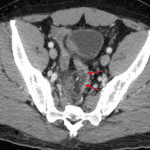

- Mural thickening of the distal sigmoid colon with adjacent hemorrhage, moreso along the right wall, and small volume pneumoperitoneum

- Short segment mural thickening of the terminal ileum with adjacent hemorrhage

- Contrast density focus in the ileocolic mesentery which increases in size on delayed images

- Small volume hemoperitoneum with a small amount of fluid extending into the left inguinal canal

Findings are concerning for focal traumatic perforation of the distal sigmoid colon related to gunshot injury. Small volume associated hemopneumoperitoneum. Likely additional site of injury and possible perforation involving the terminal ileum.

Ileocolic mesenteric injury with a small area of active bleeding.